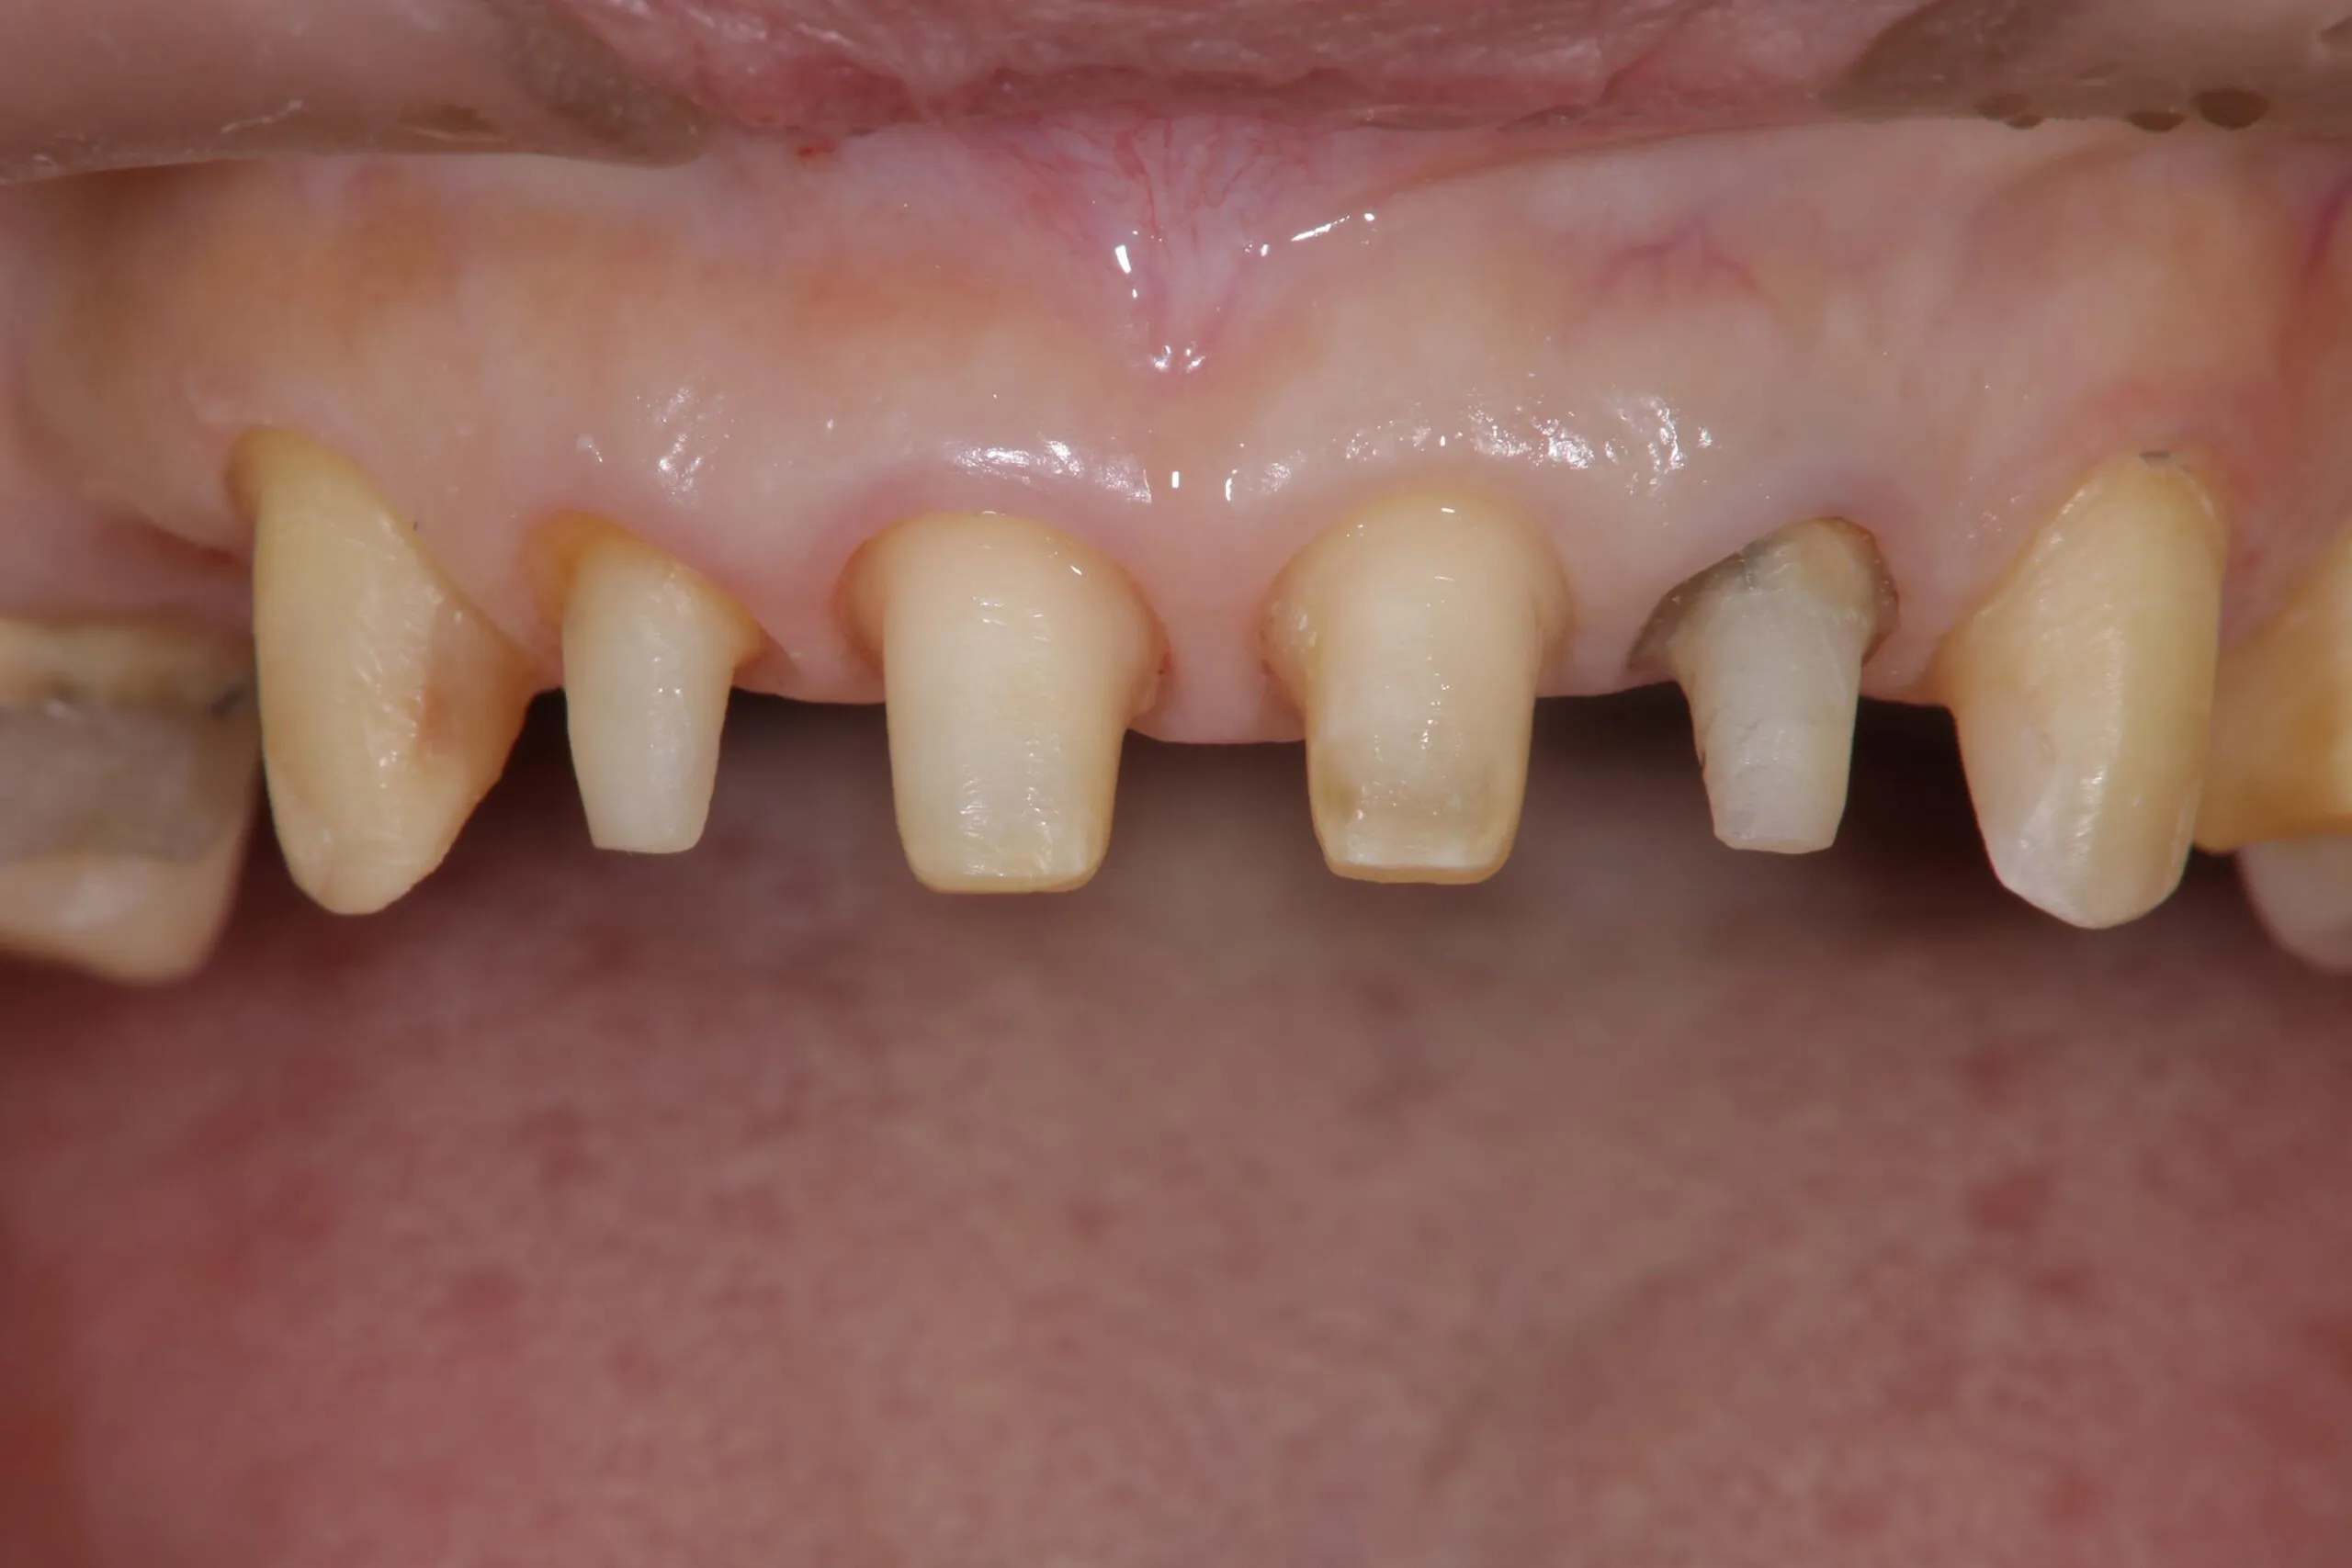

治療中